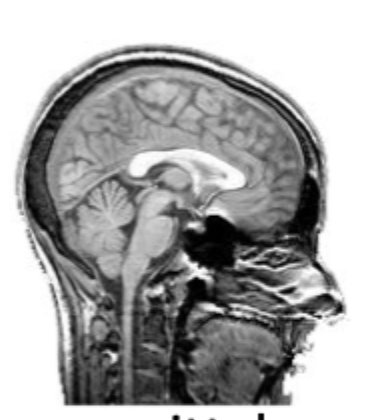

what slice of the brain is this?

the medial/midsagittal view